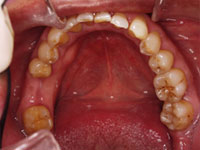

奥歯が1本もない状態のままで放置していた 患者様の事例

吉本歯科医院では、口内写真とパノラマレントゲンを撮影し、まずは顎の骨の状態まで詳しく確認しました。

口内写真.

院長の吉本の診断は以下でした。

1.奥歯がない状態で過ごしていた期間が長いため歯がない部分に隣の歯が倒れだして全体の歯並びを崩しはじめている